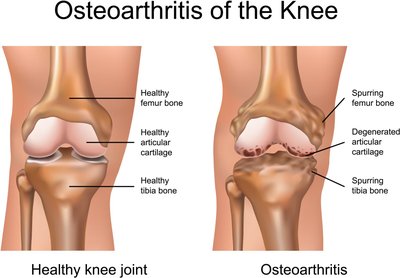

Osteoarthritis: Degenerative joint disease characterized by loss of cartilage and joint space.

Joint replacement: May be necessary if the hip or knee joint is beyond repair.